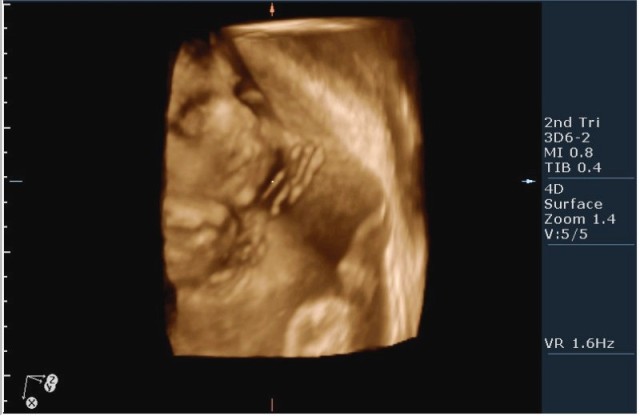

Женщина 23 года; из глухой деревни. К врачу обращалась один раз, когда забеременела. Дату последних месячных не помнит. Gravida 2, para 0. Направлена гинекологом для определения точного срока беременности и состояния плода.

1.Вентрикуломегалия/гидроцефалия (на сонограмме №1 размер задних рогов боковых желудочков 16мм при норме до 10 мм включительно;

На сонограммах головы плода визуализаируется гифдроцефалия, патогенетически связанная со спинномозговой грыжей (менингомиелоцеле) представленная в 2D и 3D режимах. В режиме Skeleton не удалось получить "картинку презентационного качества", плод начал сильно вертется; но рекоммендация очень грамотная :idea: , спасибо за ваш пост!